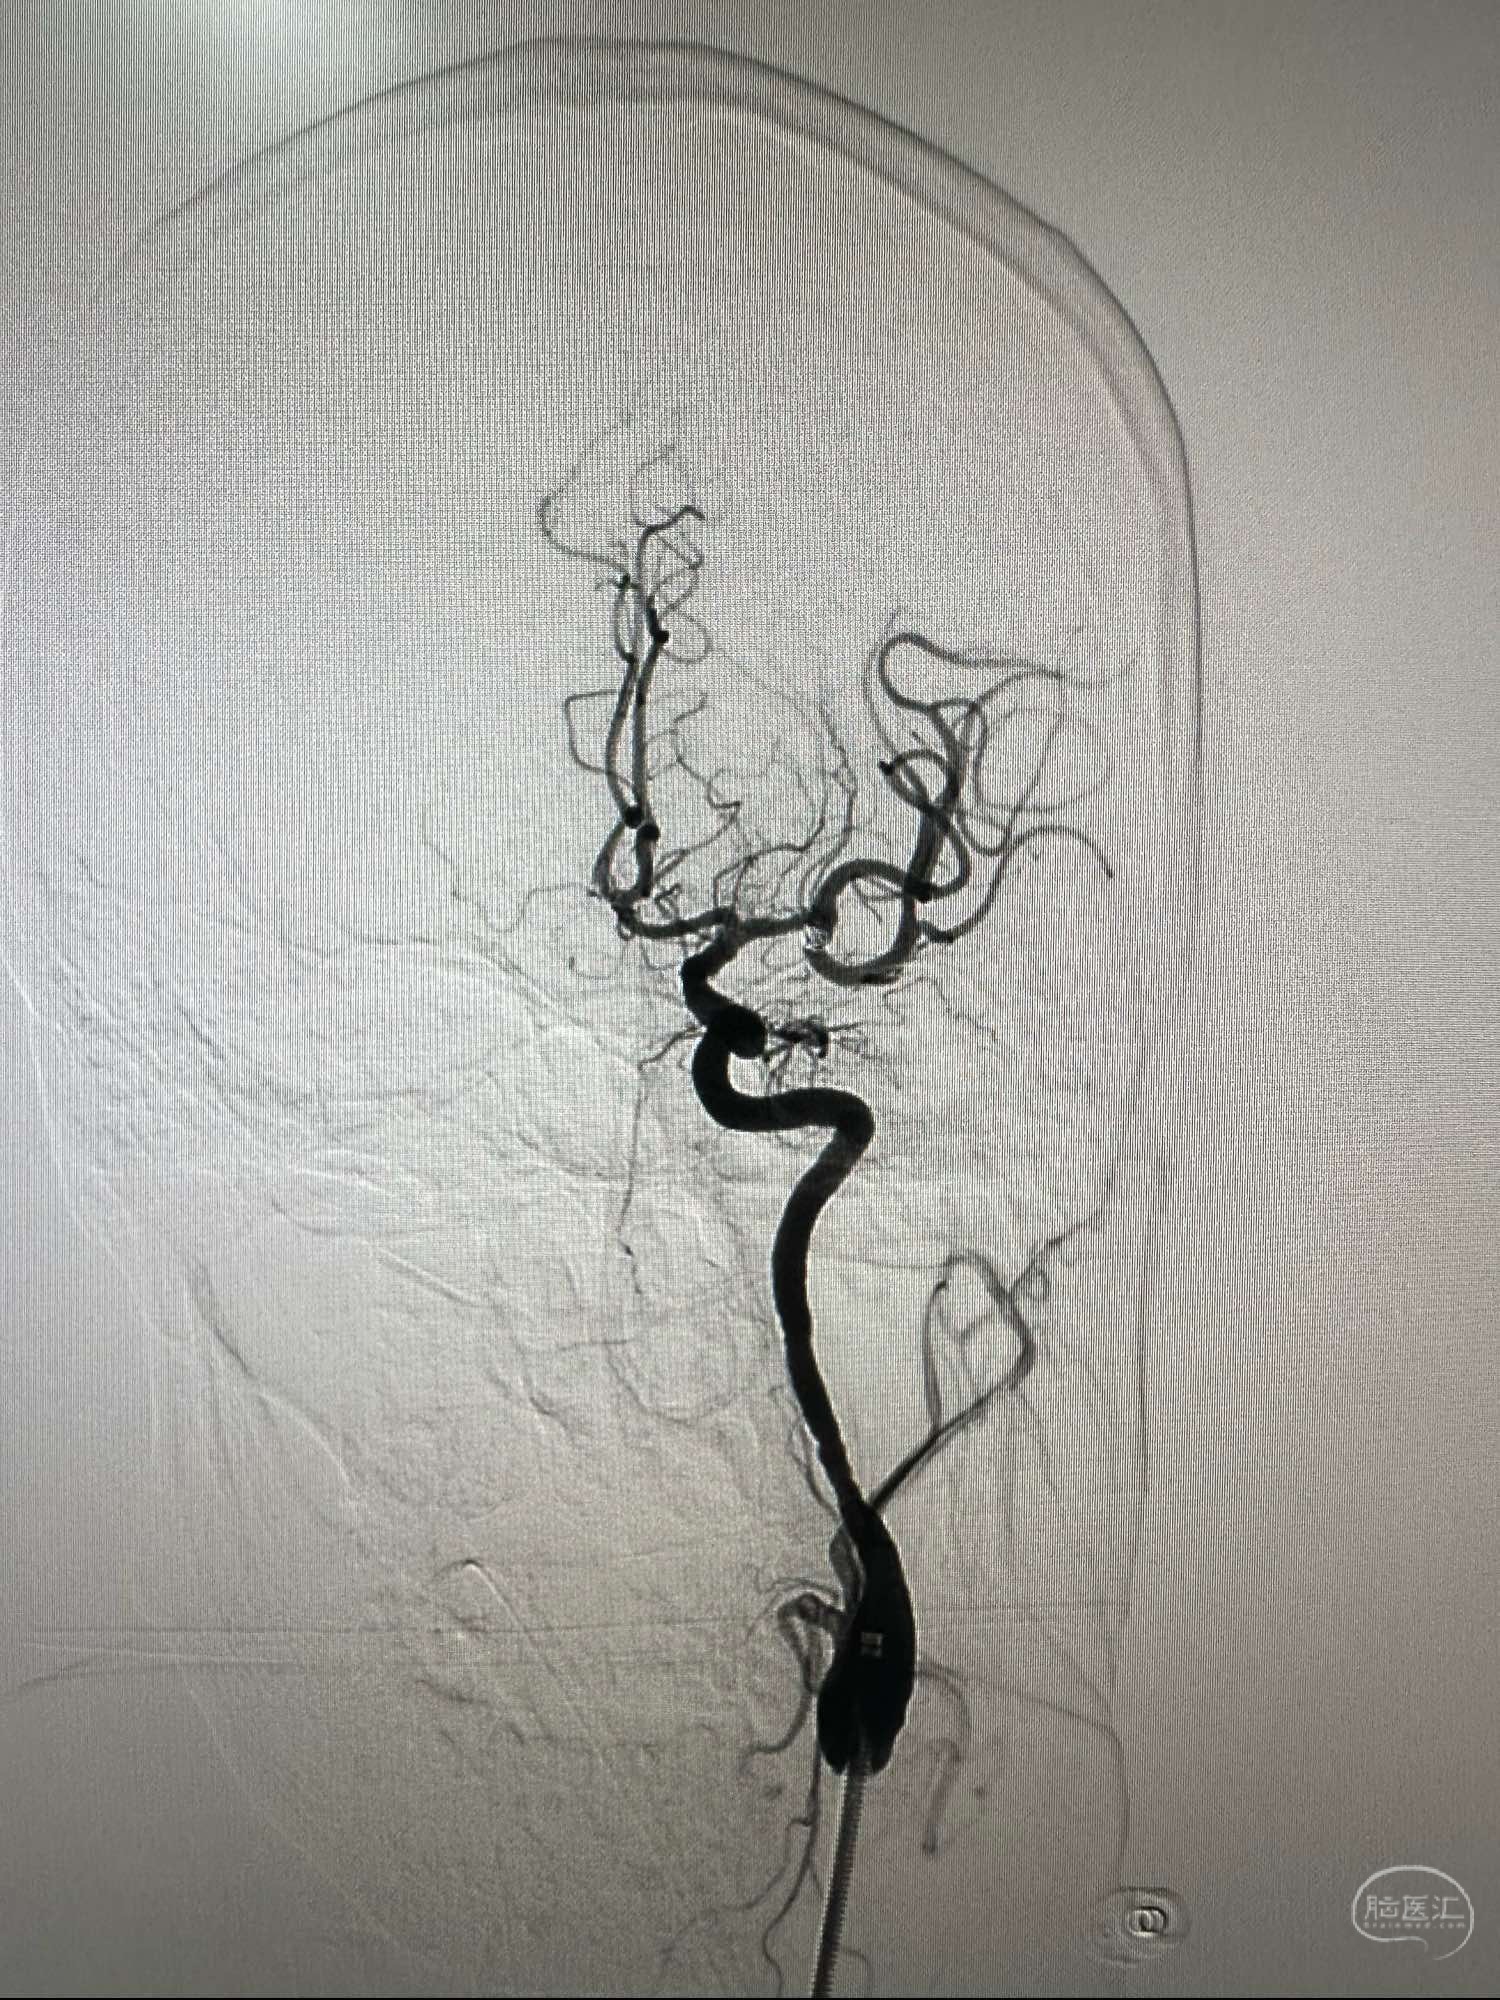

右侧颈内动脉造影正位

考虑牛角弓

左侧颈内动脉造影正位